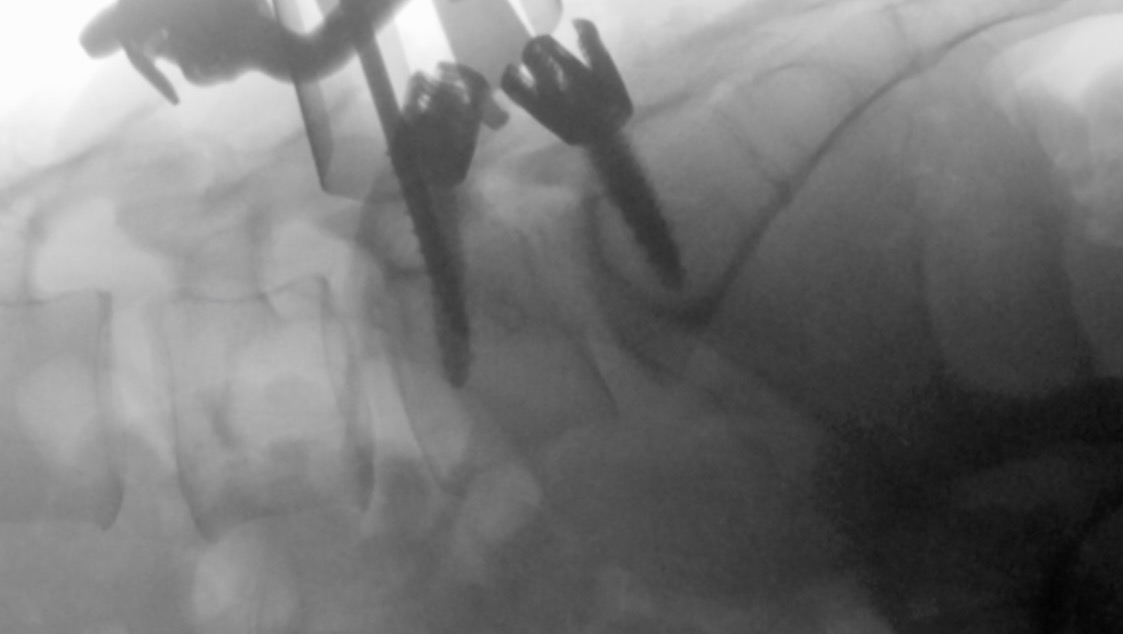

As a last resort, I had a life-changing fusion surgery this year. Being “on the other side”, I know how it felt for me these past 20 years and wish I knew certain things before. I am in a better place now to provide help, insights and to make a change for my fellow Bertolotti Warriors who didn’t get their answers and solutions yet.